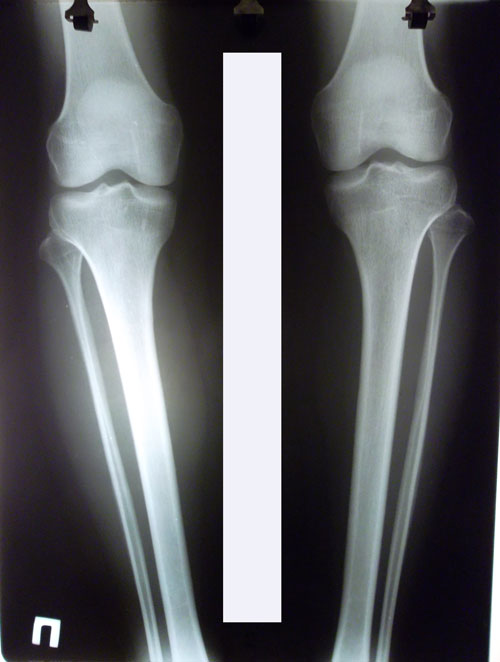

Дата операции 08.10.2015г.

Дата снятие аппаратов 11.12.2015г.

Срок лечения 62 дня.